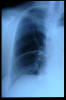

TBC pulmonar antigua